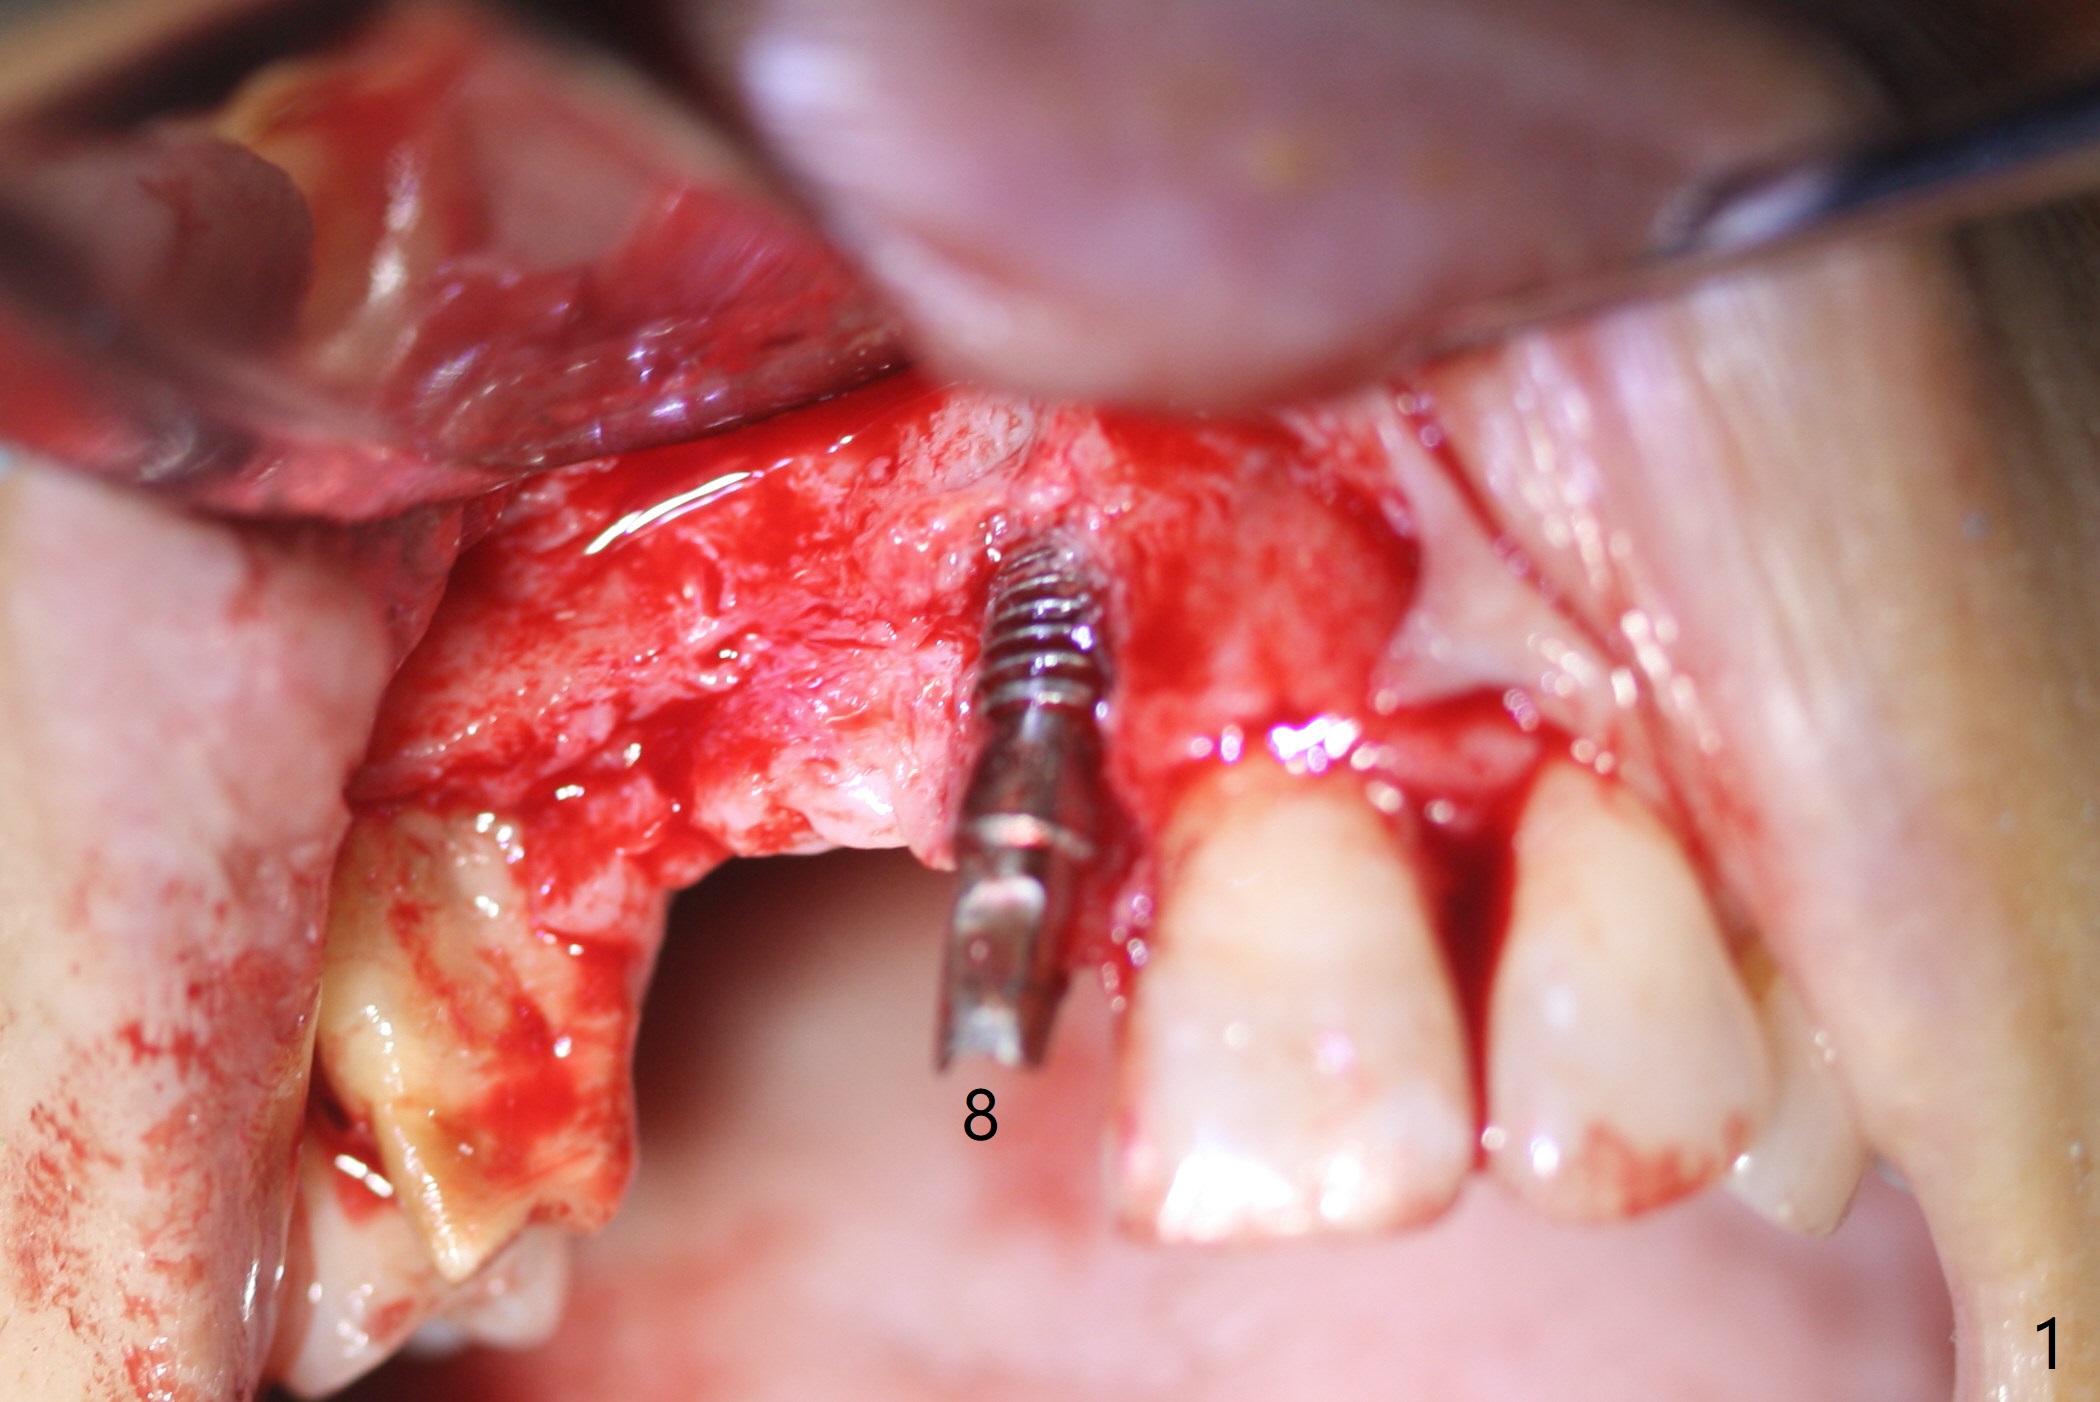

Eleven months post immediate implantation, the implant at #8 (4.5x16 mm, better smaller) is found to have thread exposure buccally (Fig.1) and distally (Fig.2). Immediately post implant removal, a 5x10 mm one is placed equi- or subcrestally distobuccally (Fig.3,4 (to prevent periimplantitis)). It is turned 4 more times later to make sure slightly supracrestally palatally, since the palatal crest is the lowest. After placement of sticky bone palatally, a 4.5(2) mm mill abutment is placed (17 mm long, Fig.5,6). The buccal flap is raised until the anterior nasal (Fig.5 N) foramen. After severing the periosteum and placement of 2 of 8 mm tenting screws (Fig.7), sticky bone (Vanilla allograft/Osteogen; block graft denies) is applied at #6 and 7 sites (Fig.8). Following palatal flap separation, the wound is closed in an apparent tension free manner (Fig.9). Periodontal dressing is applied. After wound healing, lab-fabricated provisional is delivered.